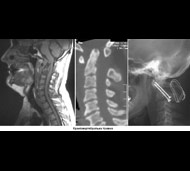

Ці обстеження включають:

- Рентгенографію. Медпрацівники зазвичай проводять рентгенографію всім травмованим, у кого є підозра на пошкодження спинного мозку. Рентген може виявити проблеми з хребцями, пухлини, переломи або дегенеративні зміни в хребті.

- Комп'ютерну томографію (КТ). КТ може надати краще зображення патології, видимої на рентгенівських знімках. Цей вид обстеження використовує комп'ютер, щоб відтворити серію зображень поперечного перерізу, які можуть виявити проблеми, пов'язані з кістками, дисками і інші.

- Магнітно-резонансна томографія (МРТ). МРТ використовує магнітну силу і радіохвилі, щоб відтворити зображення, отримані через комп'ютер. Це допомагає в ситуаціях, коли необхідно розглянути спинний мозок і виявити грижу міжхребцевого диску, згустки крові і інші утворення, які можуть здавлювати спинний мозок. Але МРТ не можна проводити пацієнтам з серцевими водіями ритму або постраждалих, яким необхідна апаратура, що підтримує життєдіяльність організму чи пристосування для витягування шийного відділу хребта.

- Мієлографію. Мієлографія дозволяє лікарю візуалізувати нерви хребта більш чітко. Після введення контрастної речовини в хребетний канал на рентгенівських знімках або КТ хребців можна виявити грижі міжхребцевого диска або пухлини. Цей тест застосовується, коли проведення МРТ є неможливим або коли мієлографія може надати важливу додаткову інформацію, яку неможливо отримати при проведенні інших досліджень.

Але постановка діагнозу на цьому не припиняється. Через кілька днів після пошкодження лікар проведе неврологічне обстеження, щоб визначити ступінь важкості ушкодження і визначити ймовірну тривалість відновлення. Може знадобитися проведення додаткової рентгенографії, МРТ або інших методів обстеження.